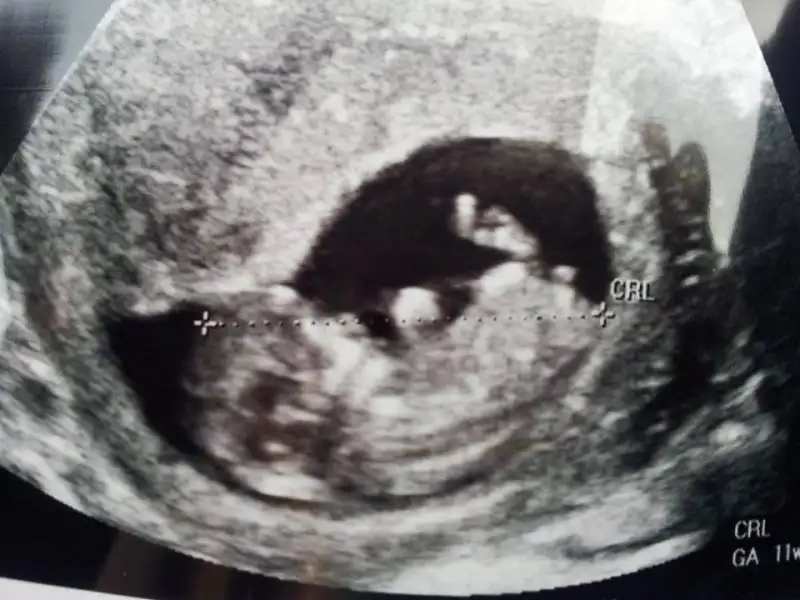

lütfen yorum yazın çok merak ediyorum 12 haftalık görüntüsü,